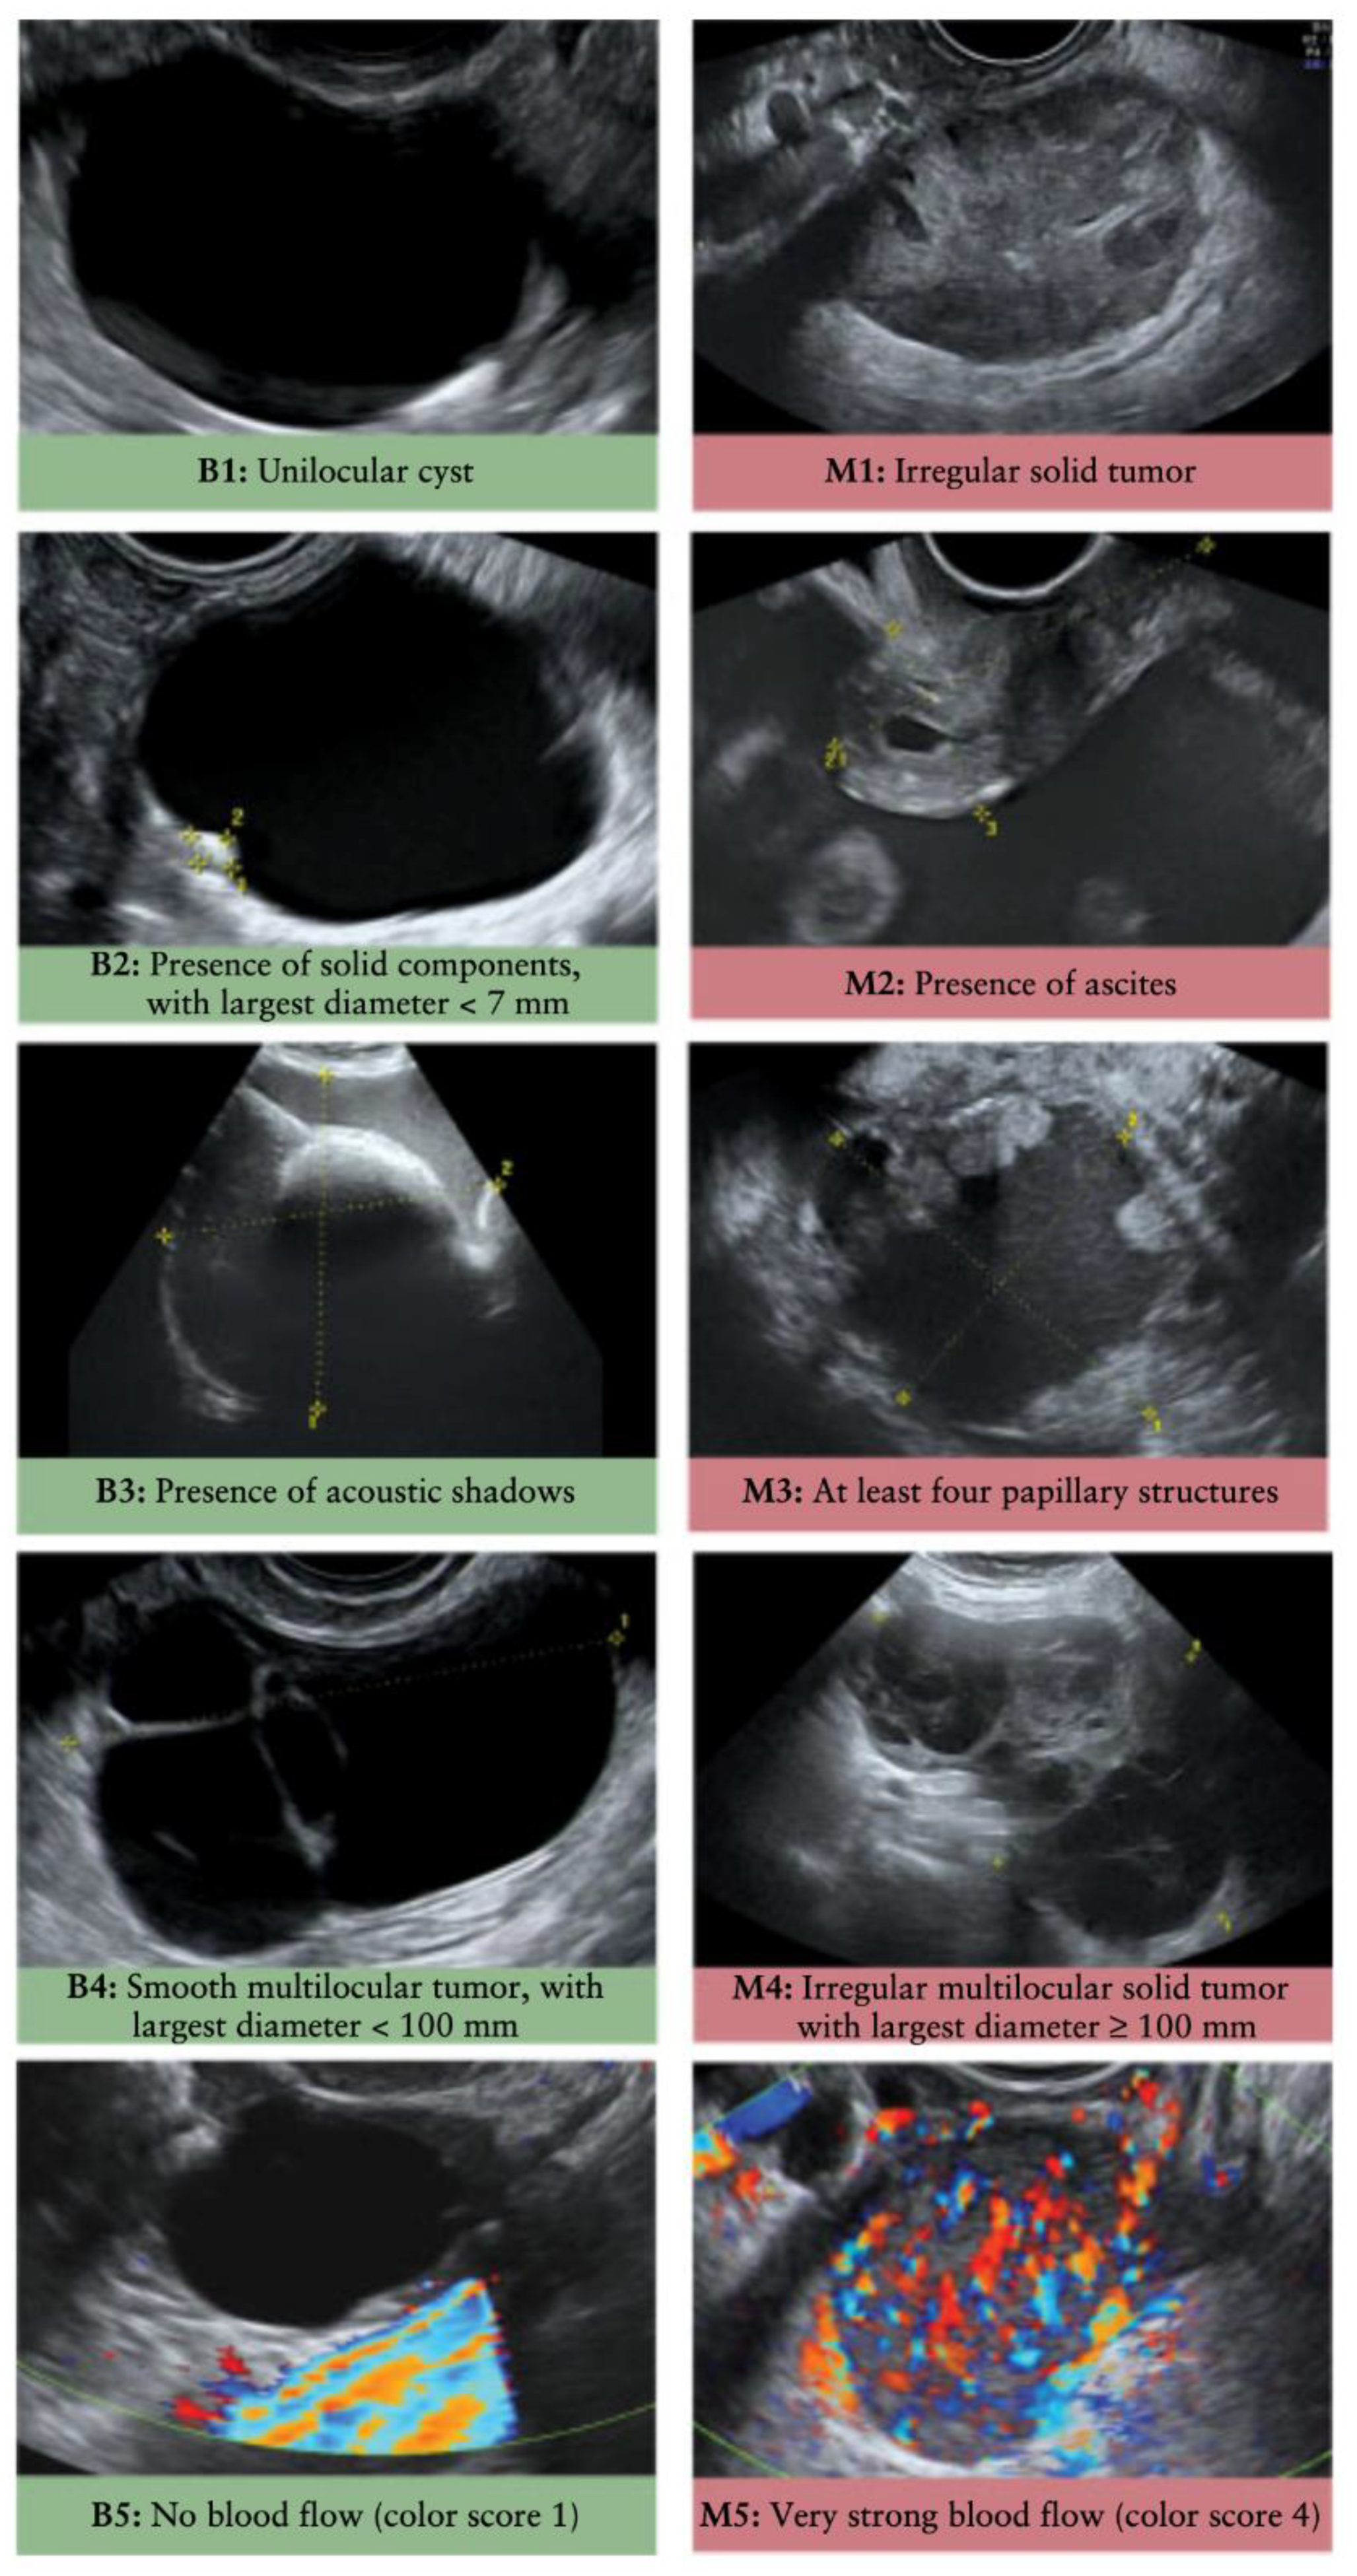

- Kaijser, J.; Bourne, T.; Valentin, L.; Sayasneh, A.; Van Holsbeke, C.; Vergote, I.; Testa, A.C.; Franchi, D.; Van Calster, B.; Timmerman, D. Improving strategies for diagnosing ovarian cancer: A summary of the International Ovarian Tumor Analysis (IOTA) studies. Ultrasound Obstet. Gynecol. 2013, 41, 9–20. [Google Scholar] [CrossRef] [PubMed]

- Meys, E.M.J.; Kaijser, J.; Kruitwagen, R.F.P.M.; Slangen, B.F.M.; Van Calster, B.; Aertgeerts, B.; Verbakel, J.Y.; Timmerman, D.; Van Gorp, T. Subjective assessment versus ultrasound models to diagnose ovarian cancer: A systematic review and meta-analysis. Eur. J. Cancer 2016, 58, 17–29. [Google Scholar] [CrossRef]